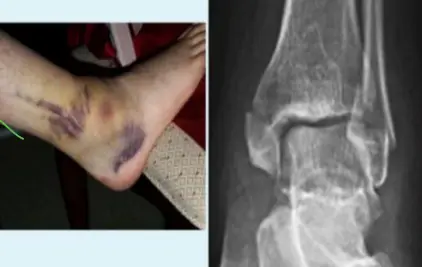

Syndesmotic Injuries

A 17-year-old male had a high ankle sprain followed by pain in his leg. X-ray films were obtained. According to the attached X-ray, which structure has been injured?

- B. Syndesmosis ligament

A 23-year-old male injured his ankle after a twisting ankle injury 2 days back. What is the most likely pathology based on shown x-ray?

Management Question: What is the management of the finding in the image?

- A. Screw fixation for syndesmosis injury

Answer 1: Ankle fracture (Suprasyndesmotic fracture in distal fibula type C with medial malleolus fracture)

Answer 2: ORIF by plate in fibula and syndesmotic screw, and screw for medial malleolus fixation

- 1: Ankle fracture (transyndesmotic fracture in distal fibula type B and medial malleolus fracture)

- 2: Open reduction internal fixation by plate in fibula and syndesmotic screw and screw for medial malleolus fixation